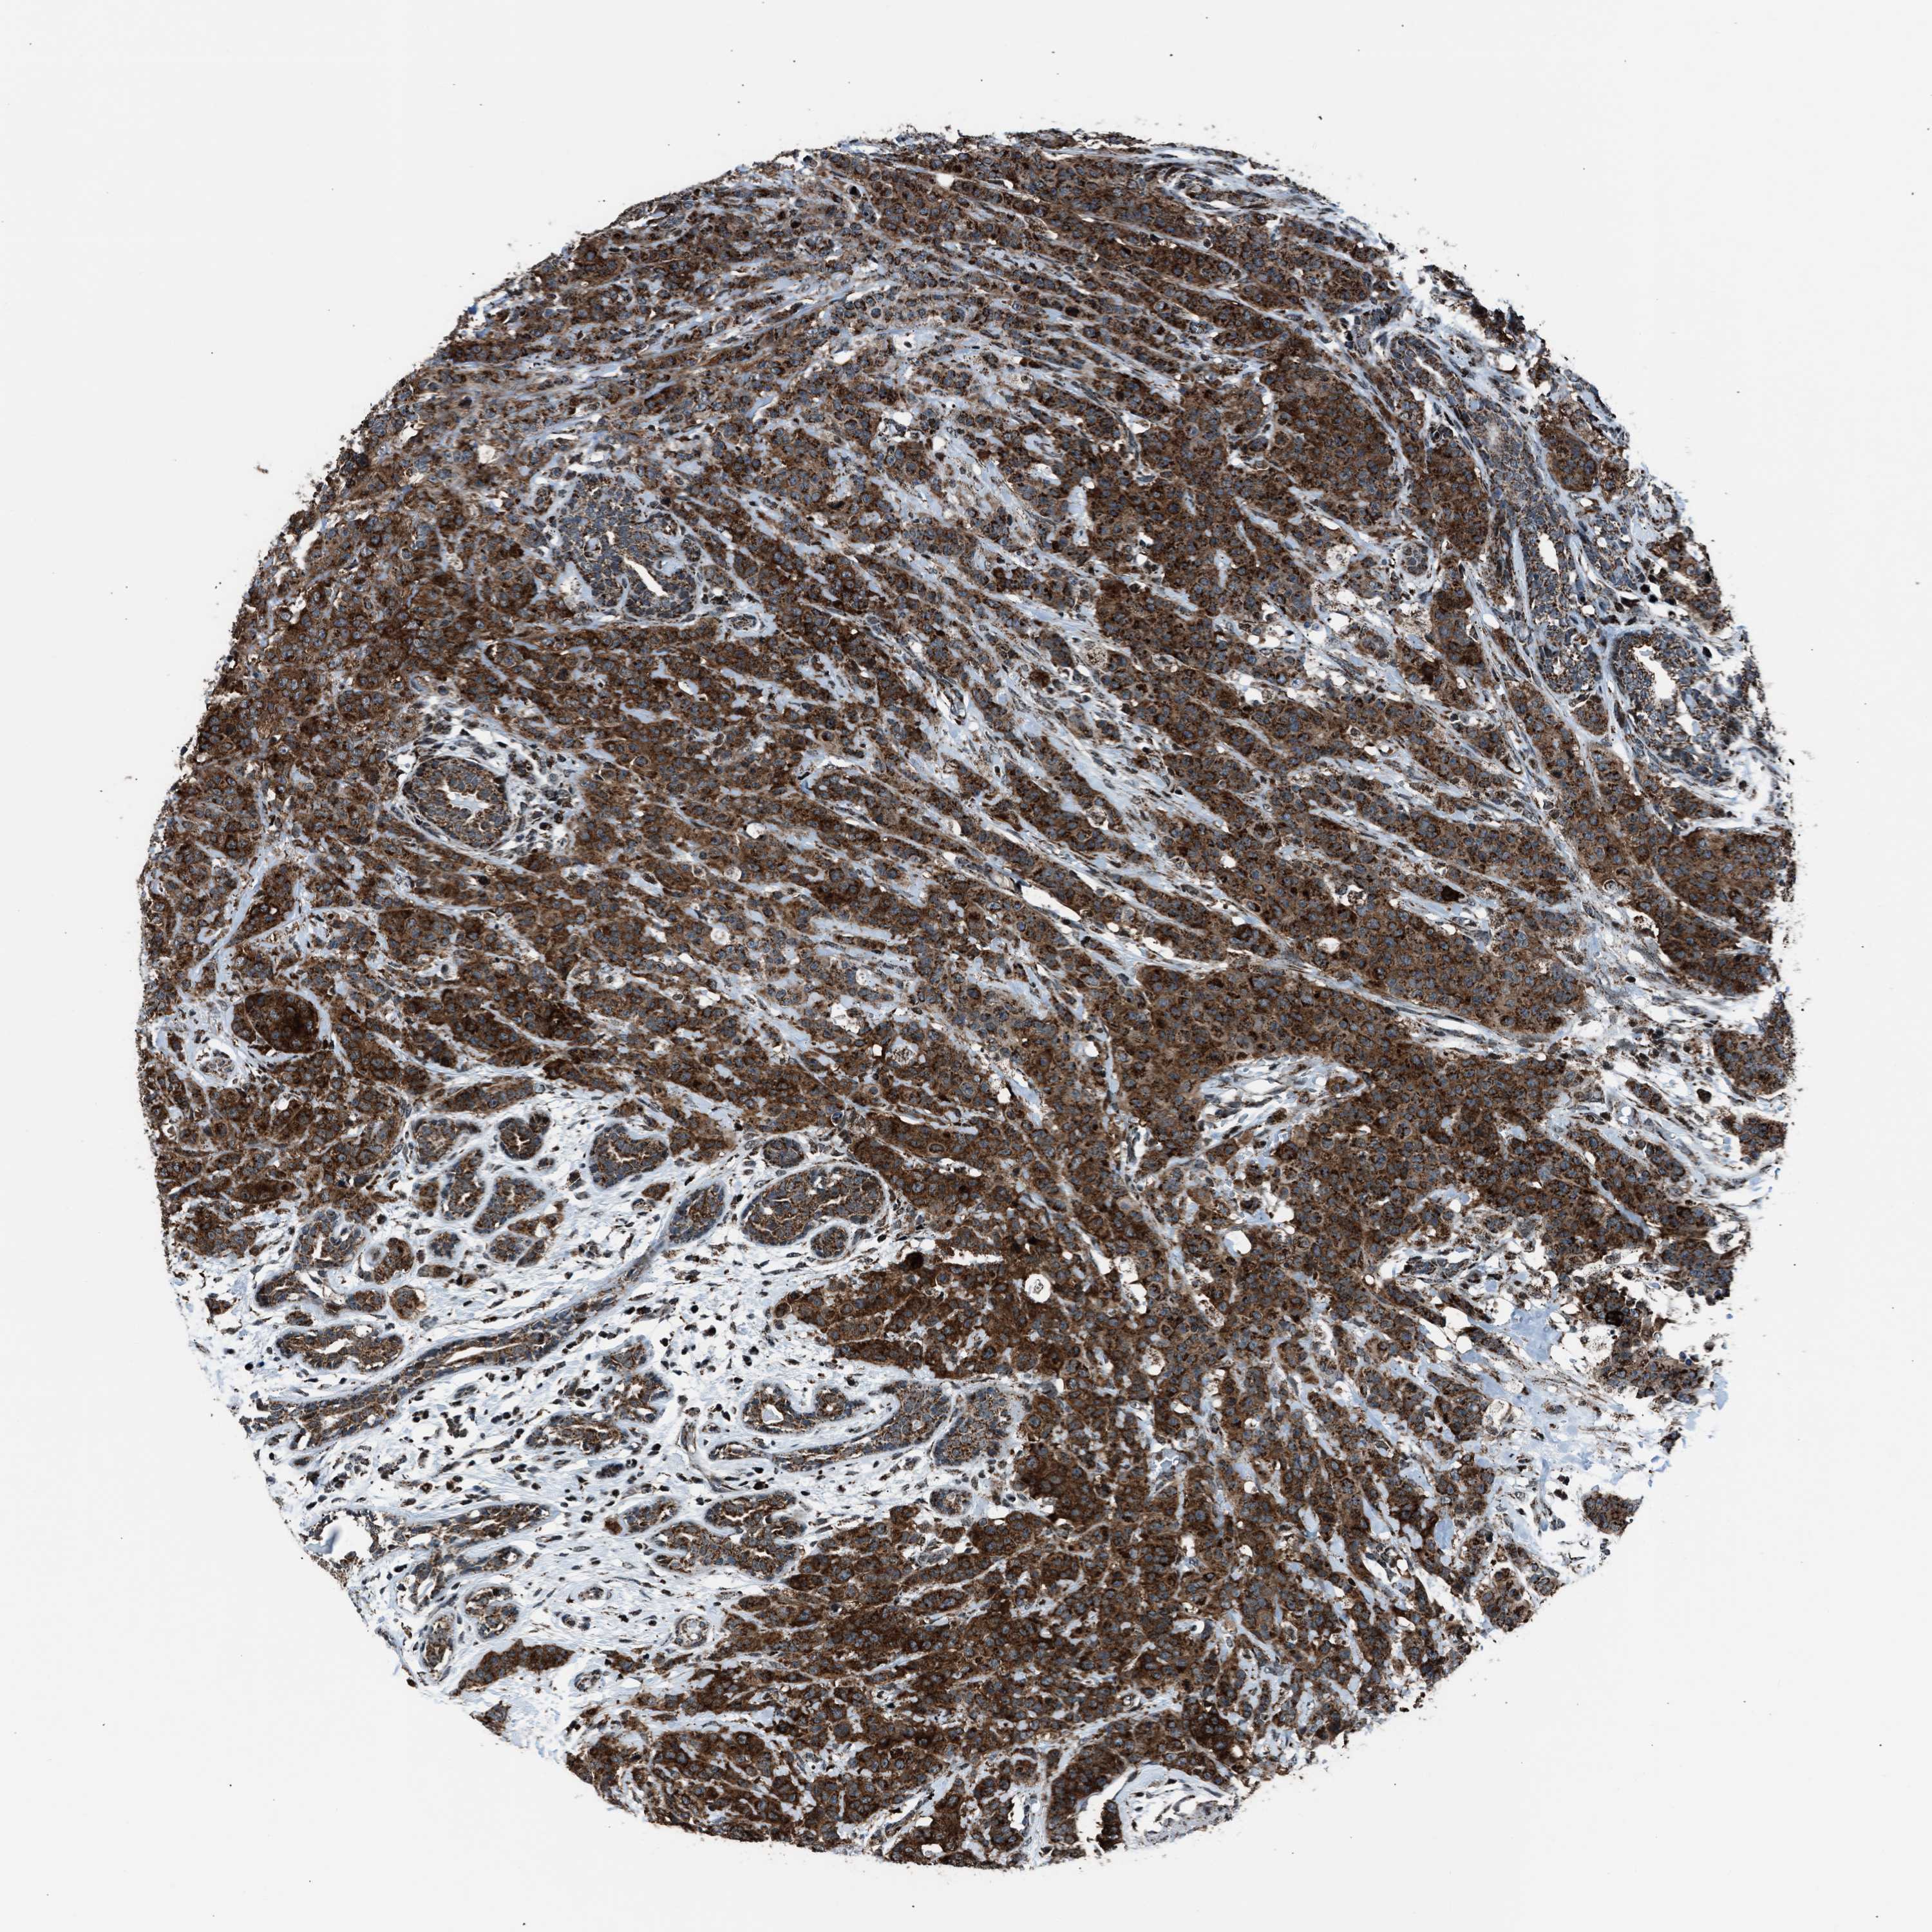

CANCER BREAST CANCER Show tissue menu

BRCA TCGA BRCA VALIDATION PROTEIN EXPRESSION

ANTIBODIES

AND

VALIDATION